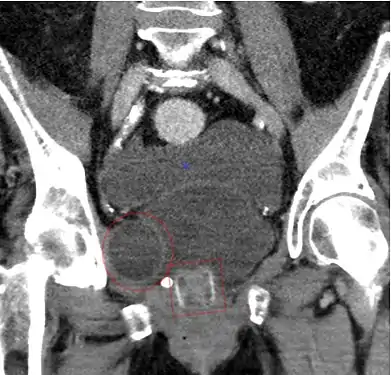

CT scan (coronal reconstruction) showing an AMS 800 in a woman